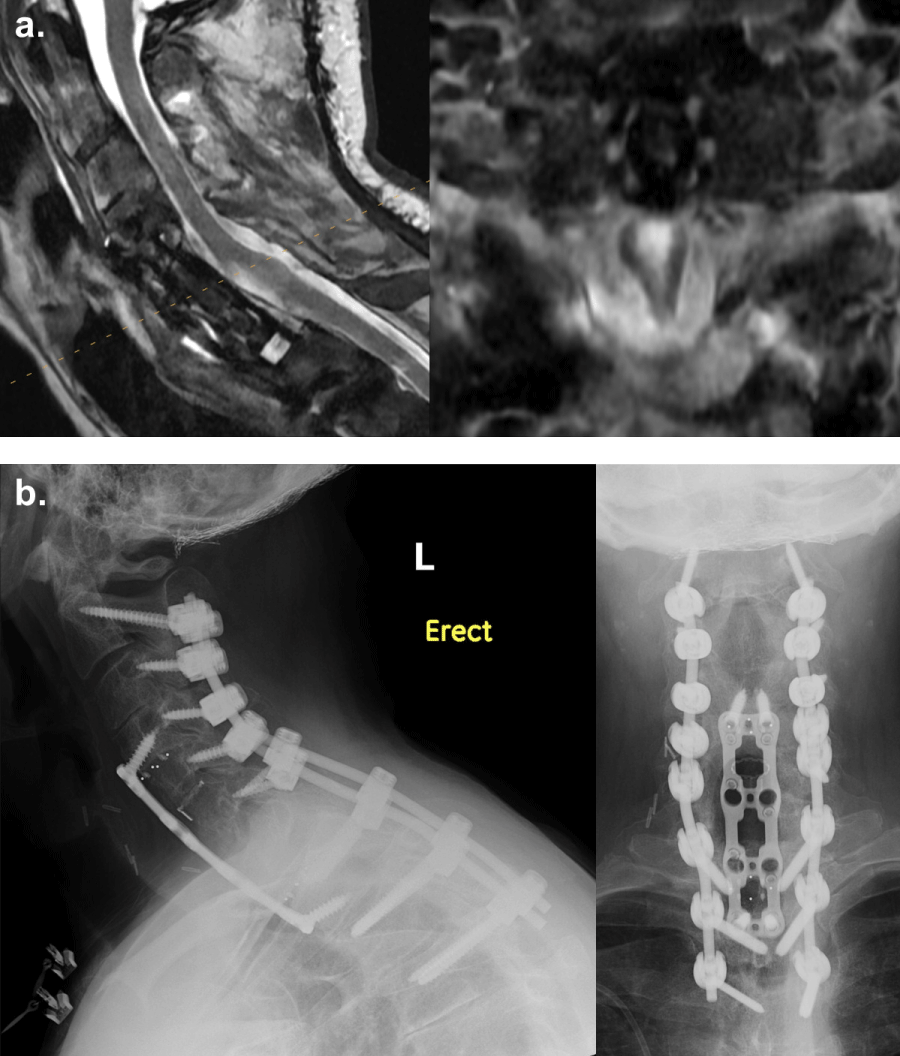

The patient experienced full resolution of the weakness in his left upper and lower extremities (Figure 4). He denied neck pain, difficulty swallowing, numbness, tingling, radiating pain, saddle anesthesia, or problems with bowel or bladder. MRI of the cervical spine obtained eleven months after the cervical ependymoma resection showed the prior C5-7 corpectomy procedure and no obvious evidence of tumor recurrence (Figure 5a). Final Pathology confirmed that the cervical lesion was consistent with a spinal metastasis from the patient’s posterior fossa ependymoma, histologic anaplasia not identified. X-rays of the cervical spine taken one year postoperatively demonstrated intact hardware without evidence of complication (Figure 5b). Other lesions, including a stable right anterior temporal lesion shown on the MRI of the brain, a dorsal intradural tumor at the T6-7 level on the MRI of the thoracic spine, and an intradural tumor at the L4 level in addition to the tumor in the sacrum on the MRI of the lumbar spine, are managed nonoperatively as the patient remains asymptomatic.

Figure 5: (a): Postoperative MRI demonstrating complete resection of the cervical ependymoma; (b): Radiographs showing intact hardware. View Figure 5